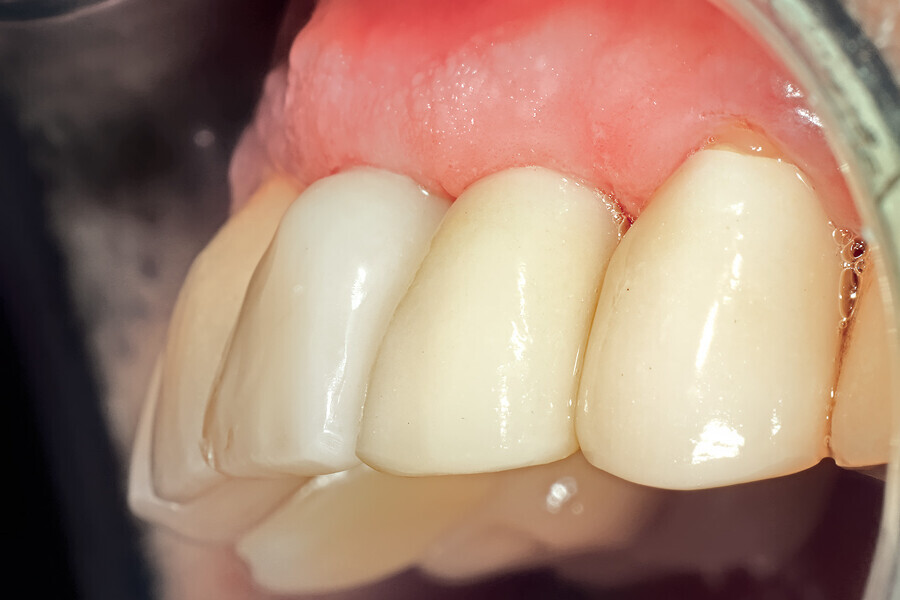

Fig. 29: The definitive restoration exhibited excellent retention of the soft-tissue profile.

Fig. 30a: The occlusal view revealed the volume maintained with

the soft-tissue cervical contours (a), and the lateral retracted view revealed an excellent soft-tissue emergence profile (b).

Fig. 30b: The occlusal view revealed the volume maintained with